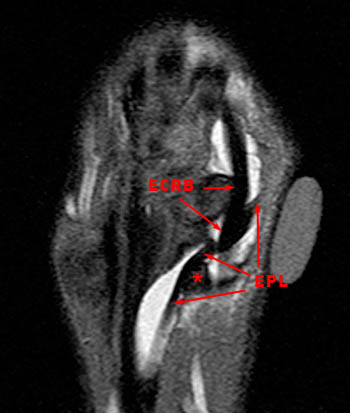

It passes through the 3 rd extensor compartment of the wrist then continues laterally towards the thumb around listers tubercle. The epl tendon is abnormally thickened with intermediate signal consistent with tendinosis. The distal intersection syndrome relates to tenosynovitis of the extensor pollicis longus epl tendon 3 rd extensor compartment where it crosses the extensor carpi radialis longus ecrl and brevis ecrb tendons 2 nd extensor compartment 1. Dr daniel j bell and greg mirt et al.